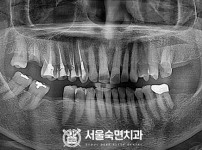

임플란트-전후사진3

치과를-선택할-때-꼭-확인하세요-서울숙면치과-임플란트-전후사진